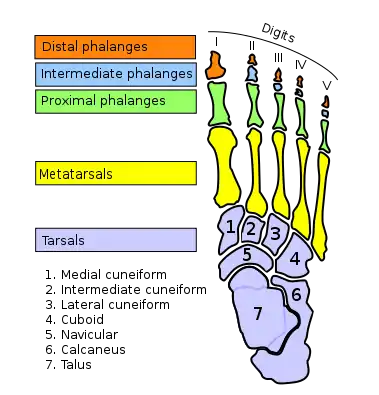

Bones of the foot (the toe bones are the ones in green, blue and orange) | |

There are normally five toes present on each human foot. Each toe consists of three phalanx bones, the proximal, middle, and distal, with the exception of the big toe (Latin: hallux). For a minority of people, the little toe also is missing a middle bone. The hallux only contains two phalanx bones, the proximal and distal. The joints between each phalanx are the interphalangeal joints. The proximal phalanx bone of each toe articulates with the metatarsal bone of the foot at the metatarsophalangeal joint. Each toe is surrounded by skin, and present on all five toes is a toenail.